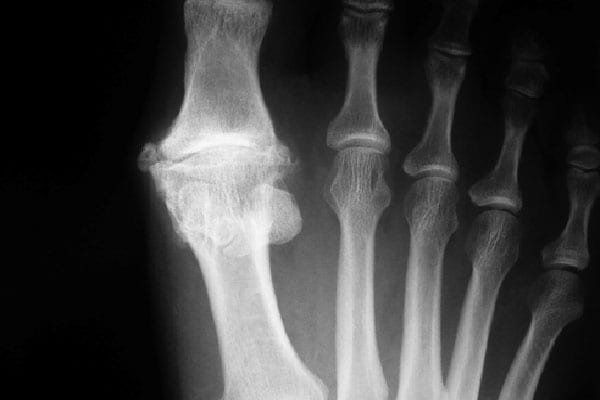

Эта деформация возникает из-за смещения костей и суставов стопы. Передняя часть стопы становится шире, кости как бы «расползаются», смещаются в стороны, подобно раскрывающемуся вееру. При этом первая плюсневая кость, которая связана с большим пальцем, сильно отклоняется кнаружи и начинает выпирать из-под кожи. Сустав большого пальца выворачивается и сам палец отклоняется в противоположную сторону (кнутри) — в сторону остальных пальцев.

При повышении уровня мочевой кислоты в организме, ее кристаллы откладываются в различных тканях. Большое скопление таких кристаллов приводит к образованию «тофуса» — уплотненного подагрического узла.

Тофусы у большого пальца ноги многие путают с косточками при ортопедическом заболевании hallux valgus .

Чаще всего тофусы возникают у больших пальцев ног, но бывают также на руках, коленях, голеностопе.

При косточках – шишка твердая, имеет четкие границы, ведь это выпирающая головка кости. По структуре она похожа на костяшки пальцев или сгиб локтя. Допускается некоторая припухлость, покраснение.

3. Угол между костями

Подтвердить смещение костей может рентгеновский снимок. Измеряется угол между первой и второй плюсневой костью. При здоровой стопе он не превышает 9 градусов. На практике рентген редко применяется для диагностики, чтобы избежать облучения пациента.

При подагре — подагрический узел (тофус) плотный, но не твердый, более похож на опухоль или отек, часто имеет расплывчатые границы и охватывает большую зону, чем область над суставом. В отличие от косточки тофус часто имеет неоднородную узелковую структуру.

2. Отсутствие смещения костей

При подагре кости не смещаются, большой палец обычно расположен правильно.